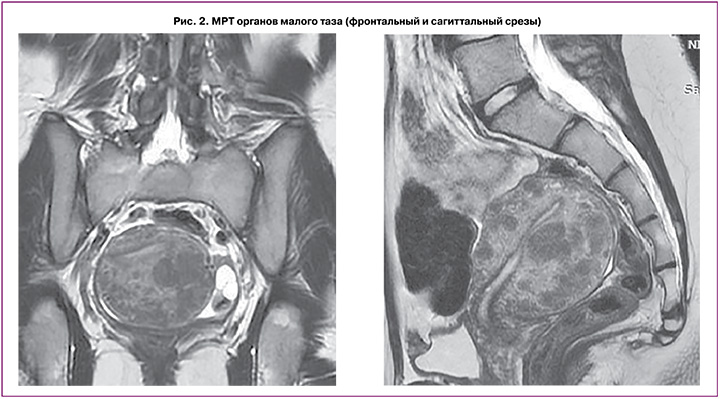

По данным описания снимков МРТ (рис. 2) выявлено, что тело матки умеренно деформировано, увеличено в размерах за счет множественных миоматозных узлов, отклонено кзади, в положении retroflexio, шеечно-маточный угол выражен. Размеры тела матки (без учета миоматозных узлов): продольный – 7,7 см, поперечный – 5,2 см, переднезадний – 6,8 см. Зональная дифференциация маточной стенки снижена. Полость матки минимально деформирована миоматозным узлом. Функциональный эндометрий толщиной до 0,2 см, не утолщен, неоднородной структуры, пристеночных компонентов не определяется. Переходно-соединительная зона с четкими неровными контурами, толщиной до 0,3 см, без распространения в миометрий, в толще миометрия определяются гипоинтенсивные сосуды, на фоне многочисленных миоматозных узлов нельзя исключить мелкие очаги эндометриоза. МР-сигнал от миометрия диффузно неоднородный. В миометрии определяются множественные, диффузно расположенные миоматозные узлы, деформирующие стенку матки, частично сливающиеся между собой (количеством более 15 шт.), размерами от 0,5 см – FIGO 4. В толще задней стенки узел до 2,2×1,6 см, с интерстициальной локализацией, близко к полости матки, с минимально выраженным объемным воздействием на полость матки – FIGO 3. По задней стенке – многочисленные узлы, без контуров, частично сливающиеся между собой, суммарно размеры зоны до 4,3×3,2 см. Все миомы без ограничения DWI. Шейка матки типично сформирована, длиной 3,0 см, цервикальный канал прослеживается на всем протяжении с небольшим количеством серозного отделяемого, слизистая равномерной толщины, области наружного и внутреннего зева – не изменены. Влагалище прослеживается на всем протяжении, стенки равномерной толщины, сомкнуты. Правый яичник расположен у боковой стенки матки, фиксирован, суммарными размерами до 4,0×2,5×2,4 см, капсула утолщена, гипоинтенсивная, строма неоднородна, фолликулы единичные, до 1,3 см. В структуре дополнительных образований не определяется. Левый яичник типично расположен, размерами до 4,0×2,9×21,7 см, фолликулы многочисленные, от 0,5 до 1,3 см, строма яичника неоднородна. В структуре – кисты до 0,9 см и до 1,2 см с геморрагическим содержимым (одна из кист с признаками ограничения DWI). Параовариально определяется утолщенная маточная труба. В полости малого таза незначительное количество свободной жидкости. Патологически измененных лимфоузлов на исследуемом уровне не выявлено. Вены параметральных сплетений полнокровны, расширены. Мочевой пузырь на момент исследования заполнен незначительно, слизистая не изменена, не утолщена. Мочеточники не расширены. Уретра не изменена. В полости таза определяются признаки минимального спаечного процесса. Брюшина полости таза, клетчатка, а также крестцово-маточные связки минимально неоднородны. Заключение МРТ-исследования: МР-признаки множественной диссеминированной миомы матки (FIGO 4, FIGO 3). МР-картина хронического сальпингоофорита, кистозные образования в левом яичнике с геморрагическим содержимым – дифференцировать между эндометриоидными кистами и кистой желтого тела с последствиями кровоизлияния. МР-картина не позволяет исключить единичные мелкие очаги наружного эндометриоза по поверхности матки и яичников, в клетчатке таза. Минимальное количество свободной жидкости в полости таза.